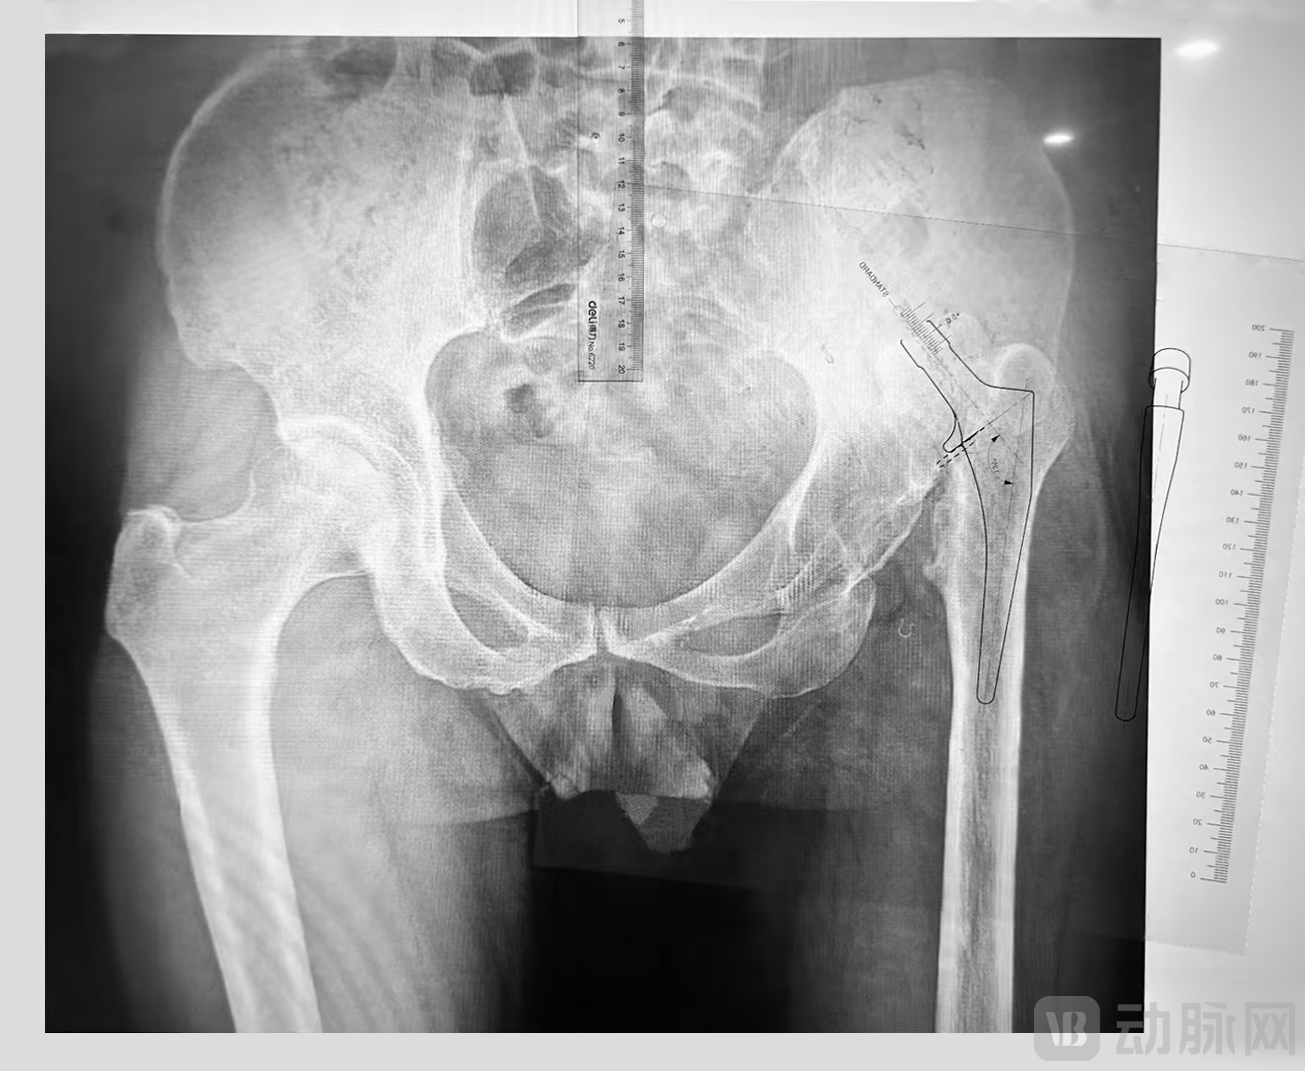

随着人口老龄化的加速,中国骨科需求日益增长。据弗若斯特沙利文统计,中国关节疾病患者超过2亿,脊柱疾病患者也超2亿,2020年中国骨科医院诊疗人数为1,602万人次。骨科手术主要包括关节手术、脊柱手术、创伤手术、运动医学手术和骨肿瘤手术等,截至2022年,中国骨科总手术量已超过650万例;预计到2030年,中国骨科总手术量将超过2,000万例。传统的骨科关节置换手术,医生在术前只能通过二维的X线胶片手动测量、反复比对,而手工量片、二维数字化量片等传统模式,受 X 线片放大率以及拍摄时投照角度的影响,得到的信息有限,准确性低。医生缺乏精准有效的辅助工具来完成术前方案的制定,常常是在脑海中去构想假体安放的位置,而术中整个过程也完全是靠手术医生的经验来判断。优质的医疗资源和大专家的手术经验难以被标准化的复制应用,病人和术者往头部医院集中,难以下沉到基层,巨大的市场需求与有限的优质医疗资源的矛盾愈加明显。人工智能关节置换手术模拟软件能够基于自主建立的各类骨科疾病的CT图像数据库以及深度学习神经网络模型,实现对不同类型关节疾病的精确分割,个体化地规划开髓点、截骨量,实现假体的前倾角、外展角与安放深度的三维重建,从而有效减少术前测量的误差。同时,能够自动计算假体的覆盖率,并精准匹配假体的规格型号。AI三维模拟软件可达到专家级精度的术前规划,从而最大幅度提高术前模拟与实际应用的假体匹配率,未来在复杂骨科手术具有巨大的临床应用潜力。医生运用该人工智能手术模拟技术能够有效提升手术的精准度[6],并可以节省手术时间及出血量、缩短患者住院时间,术后并发症的明显降低也大幅提升了患者术后满意度和预后生活的质量[7]。

传统骨科手术医生通过二维胶片进行术前X线二维模板测量

骨科手术医生通过AIJOINT®人工智能关节置换手术模拟软件进行术前3D建模与假体精准匹配